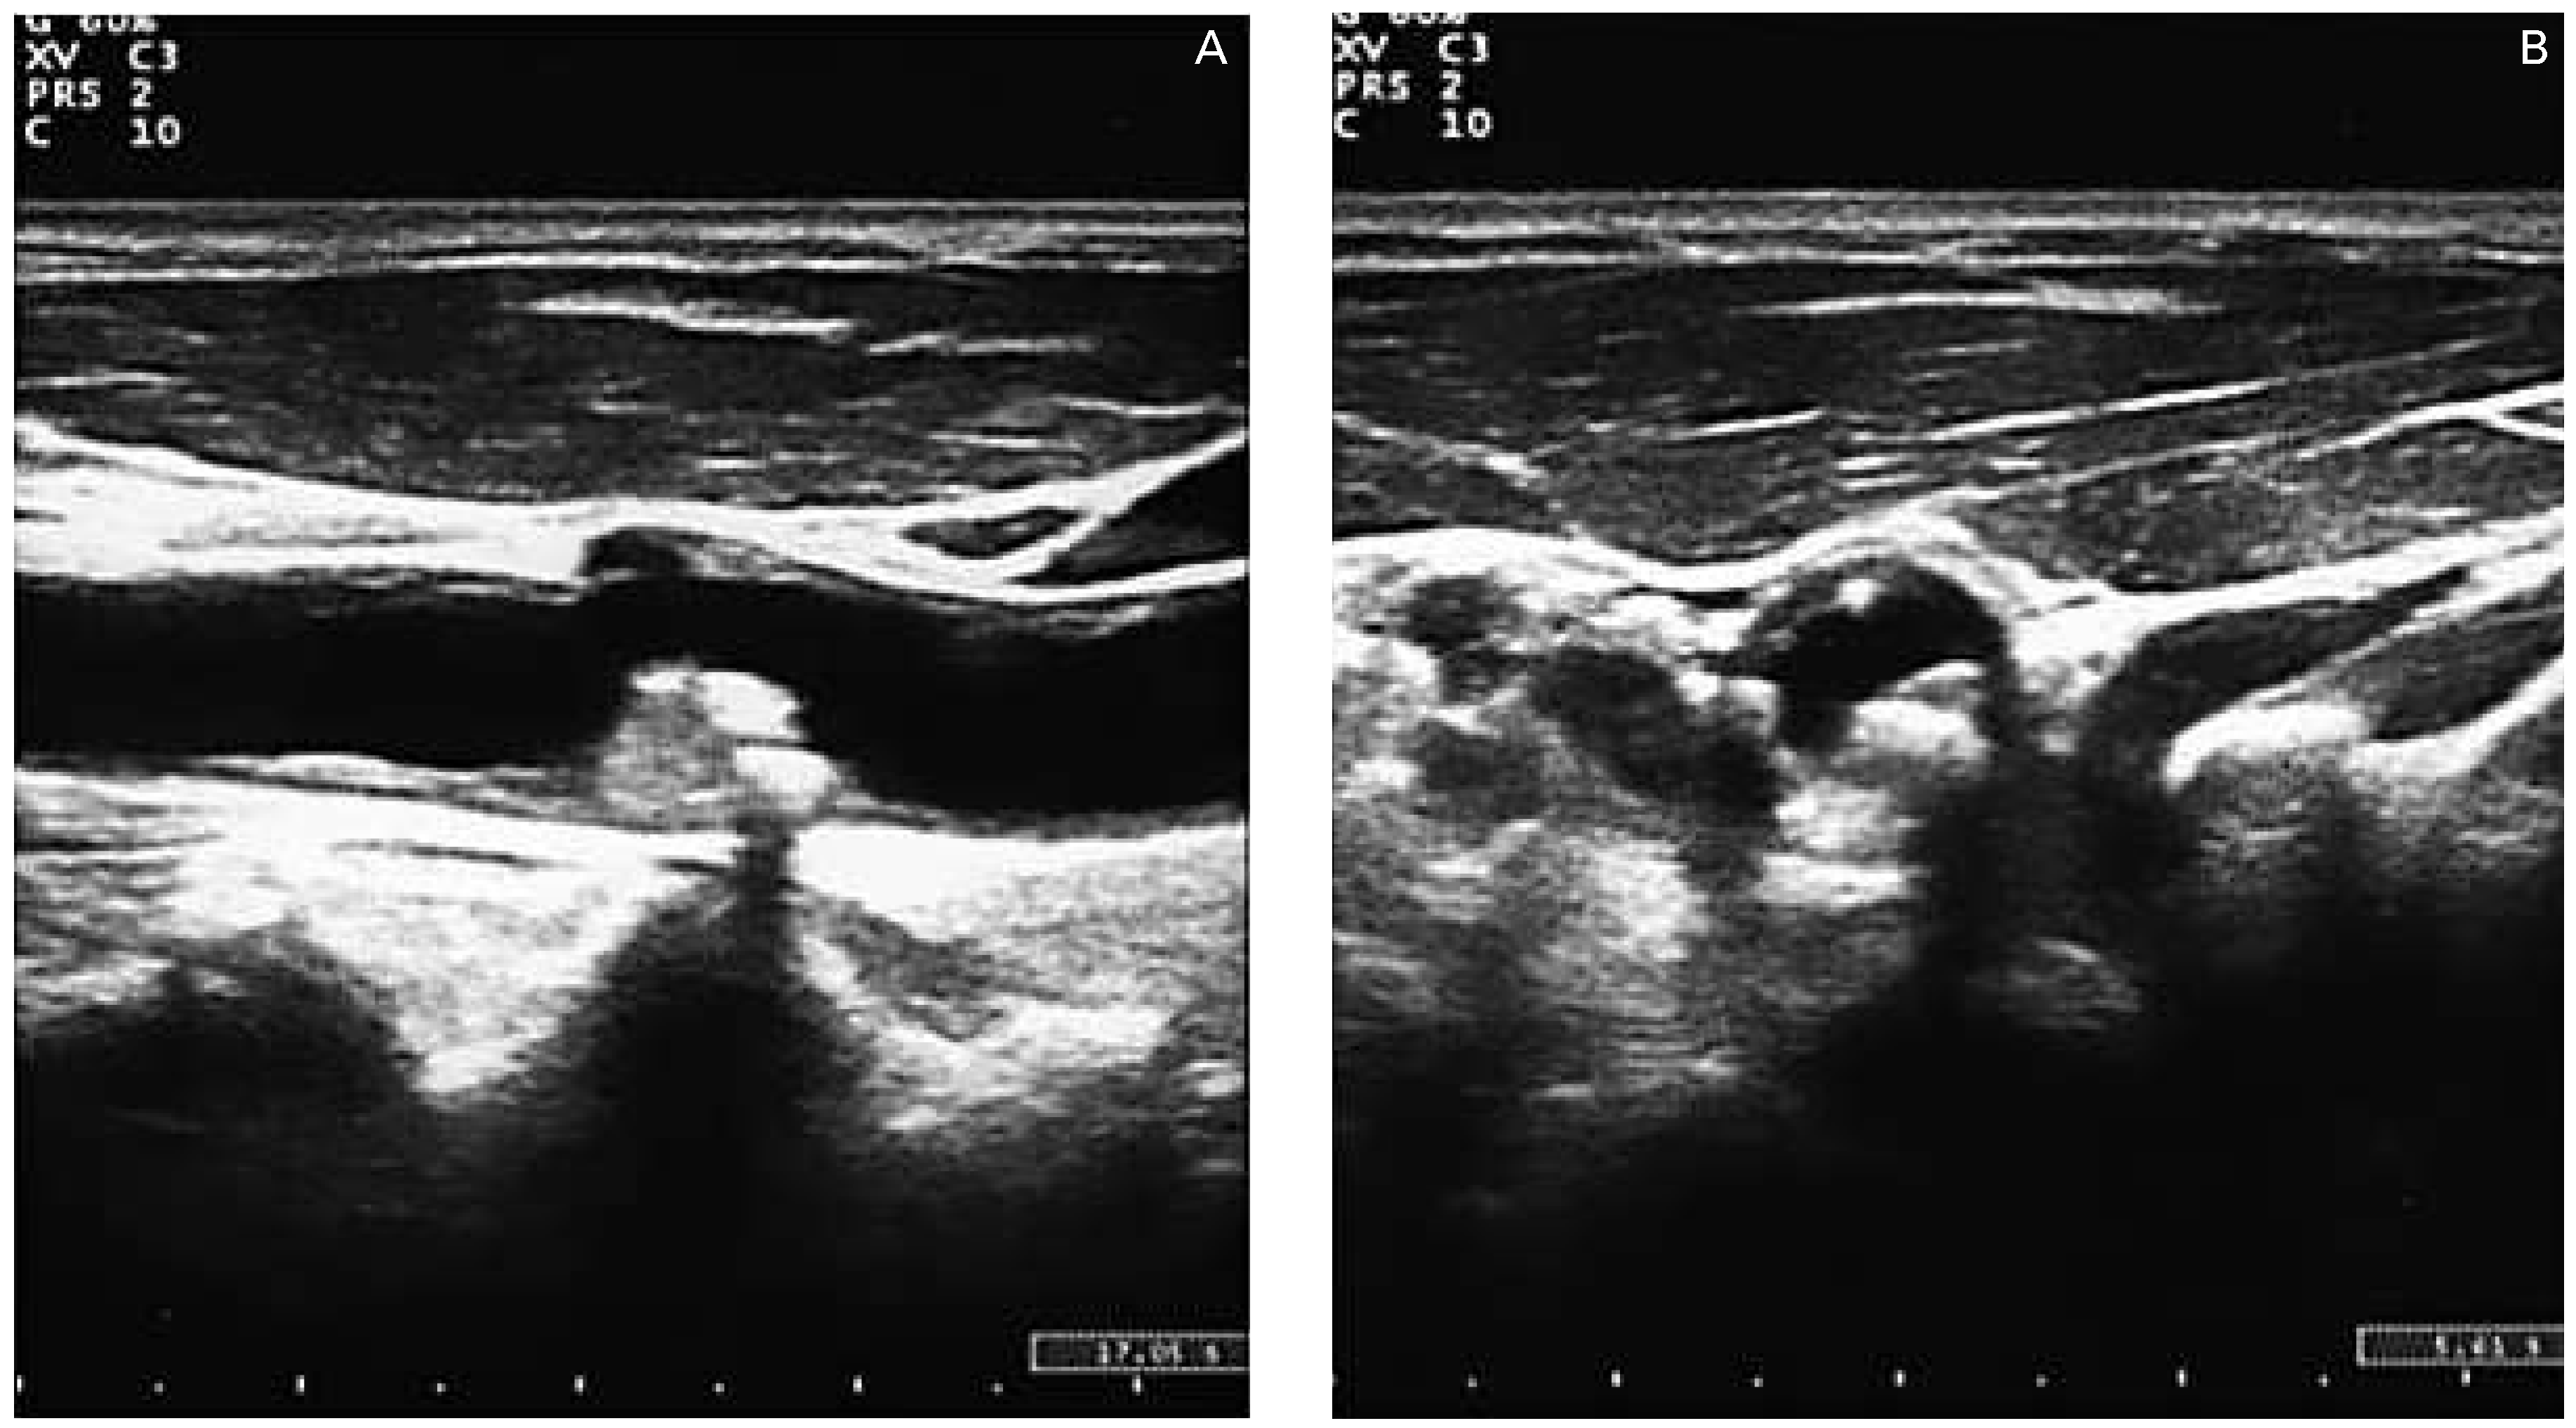

Three-dimensional ultrasound and contrast enhanced ultrasound

- An improvement in carotid assessment and cardiovascular risk prediction?